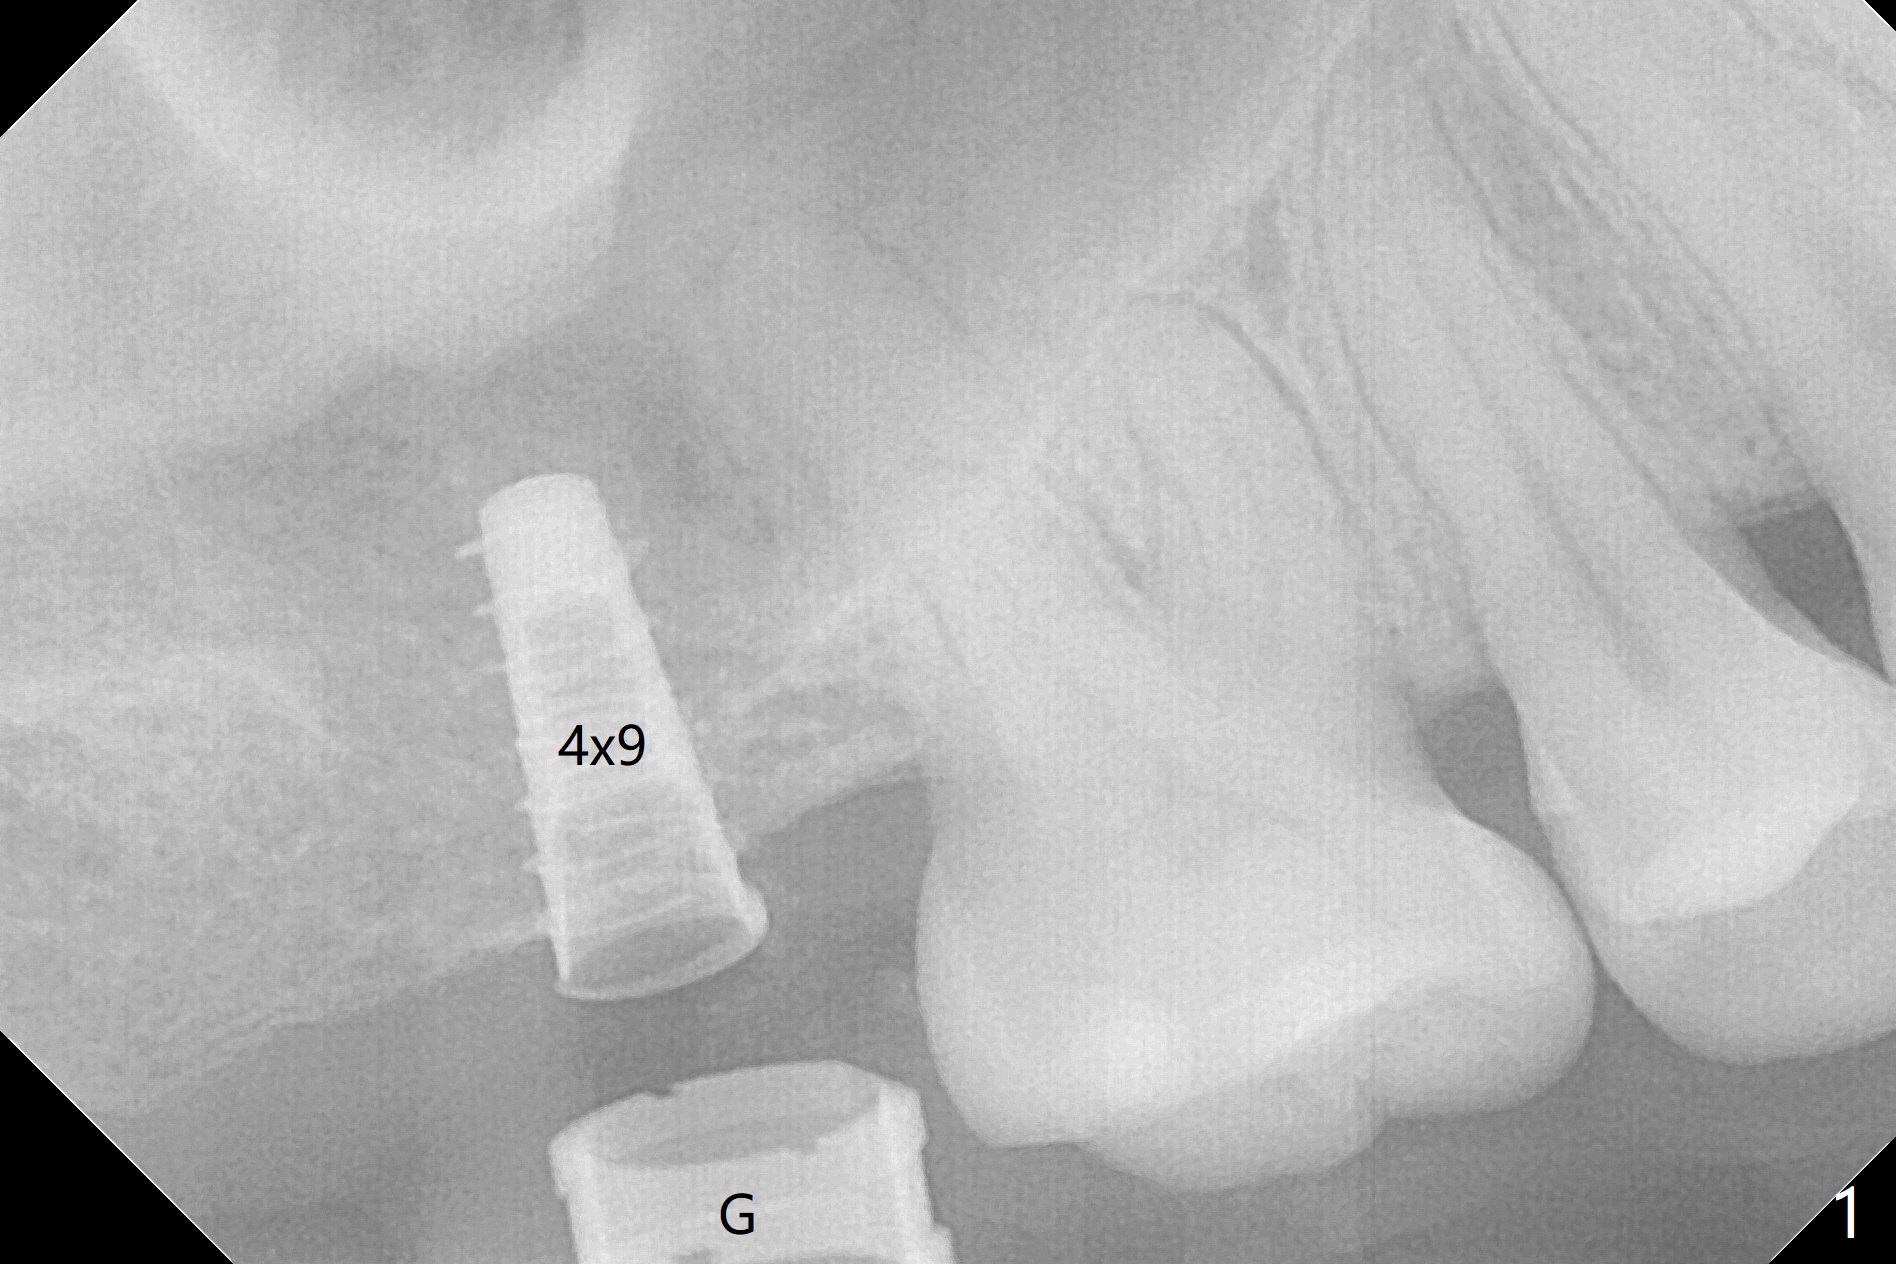

With 4-5 mm remaining bone at #2, the initial osteotomy is 4.0x3.5 mm with regular drills with sharp end. After using 3.6 mm sinus drill with round end for ~ 4 mm in depth, water lifting is conducted smoothly. After use of the same safe drill for ~ 5 mm, water lifting is done. Nose blowing indicates possible sinus membrane perforation. With insertion of collagen plug (PRF is not prepared because of thin vein), mixture of autogenous bone and allograft is lifted with 4x9 mm dummy implant with a guide (Fig.1 G). With placement of more of bone graft, a 4.5x7 mm definitive implant is placed with ~ 25 Ncm (Fig.2). Although bone graft around the implant is limited (Fig.3,4 *), the sinus membrane is lifted (in fact expanded by water) substantially (arrowheads, as compared to preop CT). The healing abutment is dislodged 1 month postop. Before impression, use sensor 1 to take PA to determine whether the abutment contacts the crestal bone or not. Take 5x5 cm CT for sinus membrane thickness. Although the bone graft surrounds the implant 3 months postop, the implant is tender when a 4.5x4(2) mm cemented abutment is being placed (Fig.5). Later a healing screw is placed (Fig.6,7). The sinus membrane has shrunk (arrowheads). Progressive loading is mandatory. The implant is uncovered with a 6x2 mm healing abutment 6.5 months postop (Fig.8). A 5.5x4(2) mm pair abutment is placed and torqued at ~20 Ncm with mild tenderness 7 months postop (Fig.9 BW). A provisional is fabricated for progressive loading because of mild crestal bone loss (*). The abutment is able to be torqued at 35 Ncm 9 months postop. Impression is taken. Return to Upper Molar Immediate Implant Trajectory II 18 Next Case with 3-4 mm Bone Screw Xin Wei, DDS, PhD, MS 1st edition 10/29/2019, last revision 02/23/2021